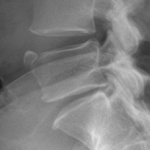

2. Limbus Bone

A limbus bone is an unfused secondary ossification center of the vertebral body (typically the anterosuperior corner), due to herniation of the nucleus pulposus through the ring apophysis prior to skeletal development. This fragment remains ununited to the vertebral body throughout the patient’s life. This can be differentiated from a fracture in that it is well-corticated, triangular, and the fragment of bone will not exactly “fit” into the defect. These fragments may be smaller than the defect of the bone (figure 2) or they may hypertrophy over time and become larger (figure 3). A limbus bone is most often asymptomatic.